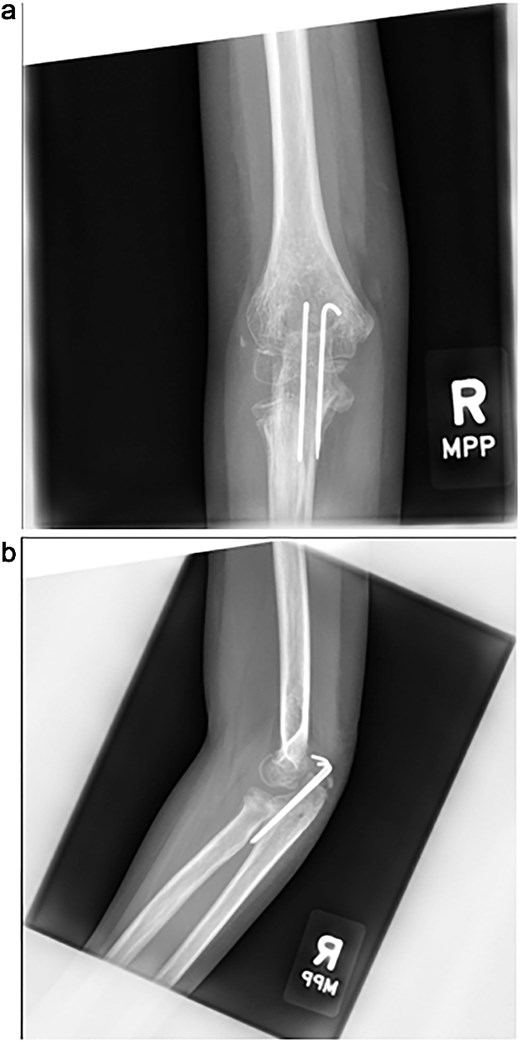

The cast was removed at 5 weeks, and radiographs confirmed maintained alignment (Fig. 4a and b), allowing the patient to transition to a hinged elbow brace. Four months after surgery, she underwent planned removal of the Kirschner wires and tension band (Fig. 5a and b). At 6 months, elbow range of motion was 10°–130° on the right, compared to 0°–140° on the left, and she reported no pain with activities. She was subsequently lost to follow-up.

(a, b) Radiographs at 5 weeks, showing maintained alignment at the time of cast removal.